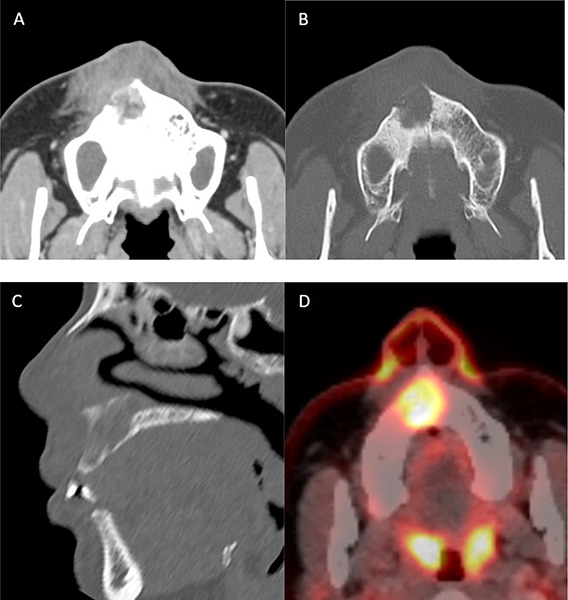

Rhabdomyosarcoma is the most common soft tissue sarcoma in children but is less frequent in adults, with the head and neck region as primary site. Magnetic resonance imaging (MRI) is the preferred diagnostic imaging tool, though its imaging characteristics are relatively non‑specific and overlap with other soft tissue sarcomas. The prognosis of rhabdomyosarcoma depends on the primary tumour site and size, with parameningeal head and neck localisations having a less favourable prognosis due to the higher risk of spread. Therefore, further imaging including brain and spinal MRI is recommended. Teaching point: The prognosis of rhabdomyosarcoma depends on the primary tumour site and size, with parameningeal head and neck localisations having a less favourable prognosis due to the higher risk of spread.

Abstract Image